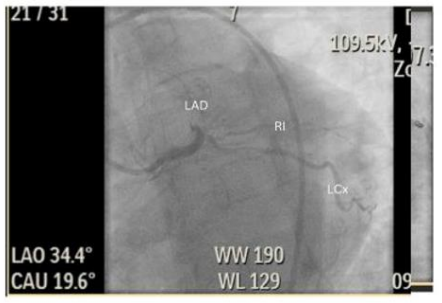

Two days subsequent to his second percutaneous coronary intervention (PCI), another rapid response was called for the patient for complaints of classical anginal chest pain. An EKG was promptly obtained which showed mild STE in AVL with ST depressions in the inferior leads/III and AVF and a Hs trop of >5000. Given these findings, he was emergently transported to the catheterization laboratory and was found to have a recurrent late*** stent thrombosis of both Left anterior descending and Ramus Intermedius stents requiring PTCA and IVUS guided optimization of both stents (Figure 8). He was then placed on the eptifibatide infusion, and this time round was started on Prasugrel, instead of Ticagrelor, along with ASA. In addition, triple anticoagulation therapy was recommended for the patient and had 2.5mg rivaroxaban daily added to his Dual-Antiplatelet therapy.

Two days subsequent to his second percutaneous coronary intervention (PCI), another rapid response was called for the patient for complaints of classical anginal chest pain. An EKG was promptly obtained which showed mild STE in AVL with ST depressions in the inferior leads/III and AVF and a Hs trop of >5000. Given these findings, he was emergently transported to the catheterization laboratory and was found to have a recurrent late*** stent thrombosis of both Left anterior descending and Ramus Intermedius stents requiring PTCA and IVUS guided optimization of both stents (Figure 8). He was then placed on the eptifibatide infusion, and this time round was started on Prasugrel, instead of Ticagrelor, along with ASA. In addition, triple anticoagulation therapy was recommended for the patient and had 2.5mg rivaroxaban daily added to his DualAntiplatelet therapy.